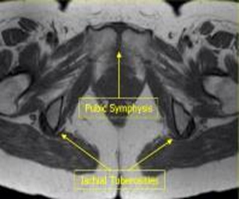

AXIAL T2 SPAIR TSE 3-4 mm 0.5-1mm SPAIR both hips 1 cm above acetabulum thru symphysis pubis

MRI Pelvis Sports Hernia WO MSK Protocol image 1